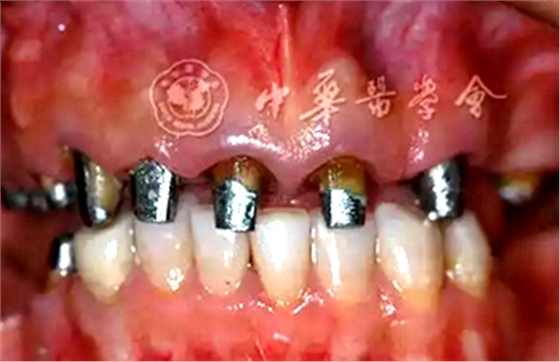

拆除上下頜修復體,根管治療或再治療,控制牙髓及根尖周感染,為樁核冠修復創(chuàng)造條件。

2.牙周基礎治療:

口腔衛(wèi)生宣教與指導;齦上潔治、齦下刮治和根面平整;初步控制牙周炎癥、恢復牙齦健康(圖3)。

圖3 牙周基礎治療后患者牙齦炎癥得到初步控制